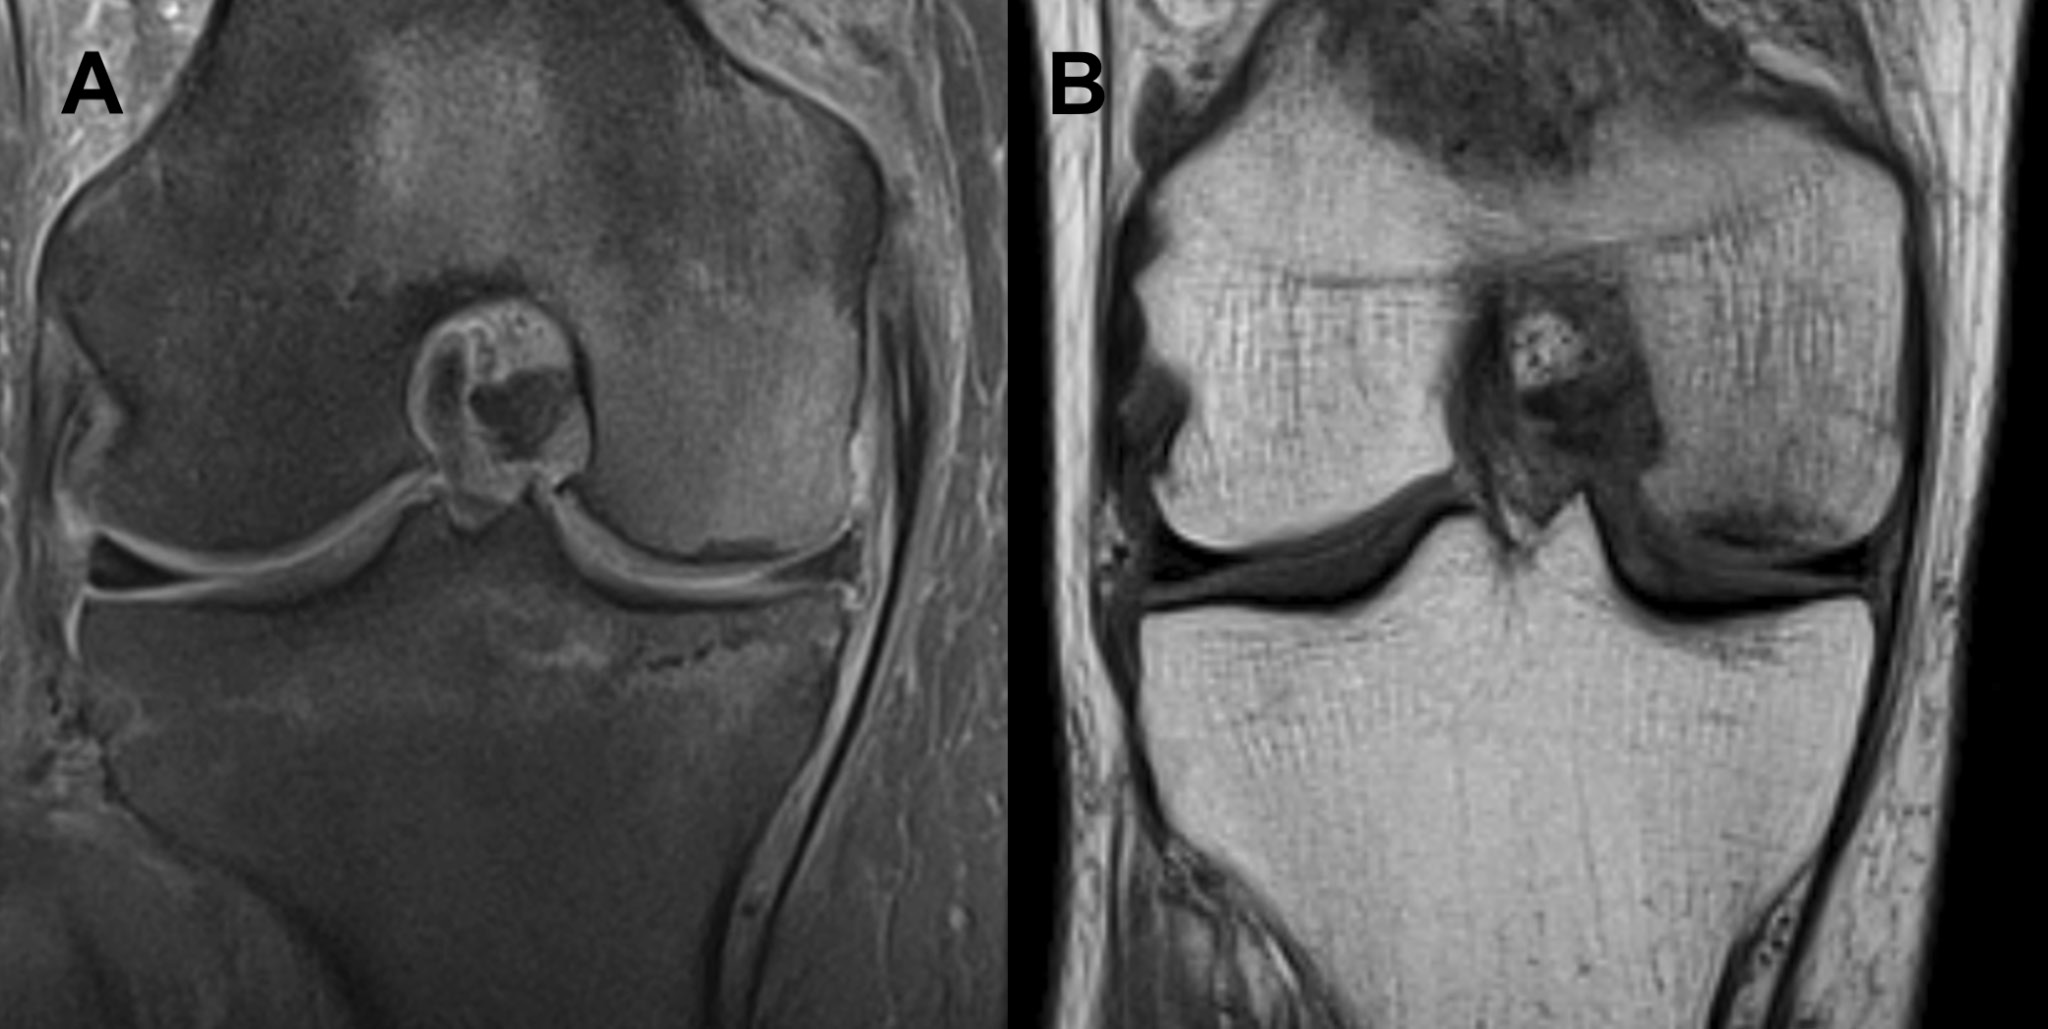

On clinical examination, the patient had a full range of motion, with a stable joint, with pain during extension and near full extension. In addition, the patient experienced pain upon palpation of the MFC and joint spaces of the affected knee. Varus stress test applied to the knee with the leg in 10° flexion also elicited pain. The knee axis was recorded as less than 5° of varus. Magnetic resonance imaging of the knee 4 weeks after the onset of symptoms revealed diffuse high signal in the entire MFC, suggesting an accumulation of edema in the bone marrow (Figure 4).

Full remission of symptoms was achieved after approx. 3 weeks of such conservative treatment. Follow-up MRI 10 weeks after presentation revealed near-complete loss of signal in the MFC (Figure 5). There were no adverse or unanticipated events.

Fig. 4. Magnetic resonance imaging (MRI) coronal view of the right knee (Case 2) performed in the symptomatic period. There is diffuse increase in signal in the medial femoral condyle in both (A) short tau inversion recovery (STIR) fast spin echo (FSE) and (B) longitudinal relaxation time (T1) sequences. It is noteworthy that the signal intensity in the subchondral bone is only slightly affected in the (B) T1 sequence. Edema of the soft tissues on the medial side of the joint is also clearly visible

Fig. 5. Follow-up magnetic resonance imaging (MRI) coronal view of the right knee (Case 2) performed after the resolution of symptoms. The signal in the medial femoral condyle in both (A) short tau inversion recovery (STIR) fast spin echo (FSE) and (B) longitudinal relaxation time (T1) sequences is almost normal. It is noteworthy that there is no visible soft tissue edema